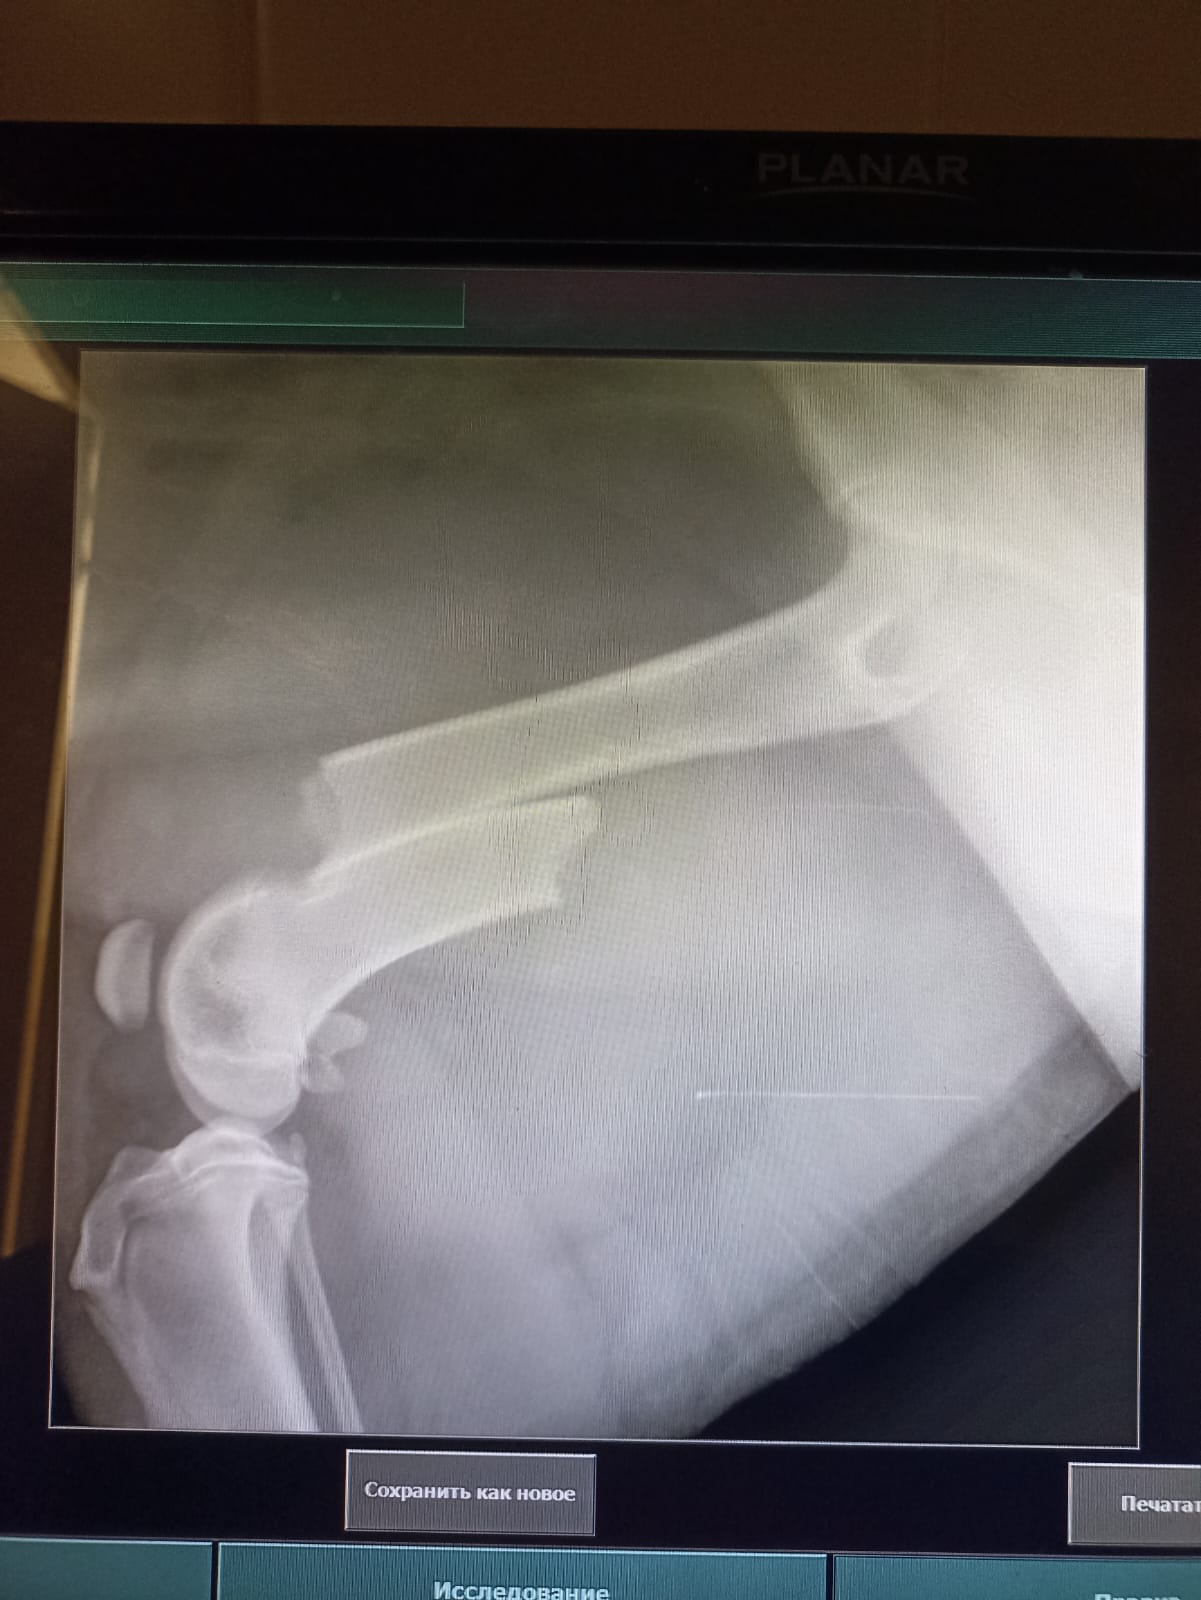

Волонтёр привела молодую суку ризена со сломанной лапой в клинику к Насте pani Stasi. Вроде перелом не сильно свежий.

Ногу будет хирург смотреть и может в ближайшее время прооперируют.

Если не дать образоваться мозоли, то все должно встать на место и будет хорошо.

Но чем больше тянуть, тем тяжелее совмещать кость....

Поэтому, чем быстрее, тем лучше. Если никаких других подводных камней нет.

Её забрала заводчица. И что-то там у них случилось, то ли лошадь понесла, то ли что, в общем, собака перепрыгивала через телегу и сломала лапу. У заводчицы тоже ключица сломана, может ещё что-то.

Операцию сделали, собрали лапу на две пластины. Выписка попозже будет.

Да, задняя правая сломана.